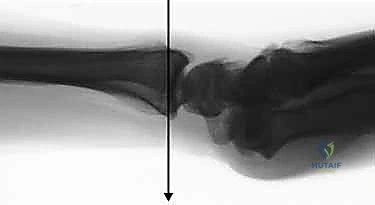

- الأشعة السينية (X-rays):

هي الخطوة الأولى لتقييم الكسر. يتم أخذ صور من زوايا متعددة (أمامية خلفية، جانبية، ومائلة) لتحديد موقع الكسر الأساسي ودرجة الانزياح والتقصير في عظم الكعبرة.